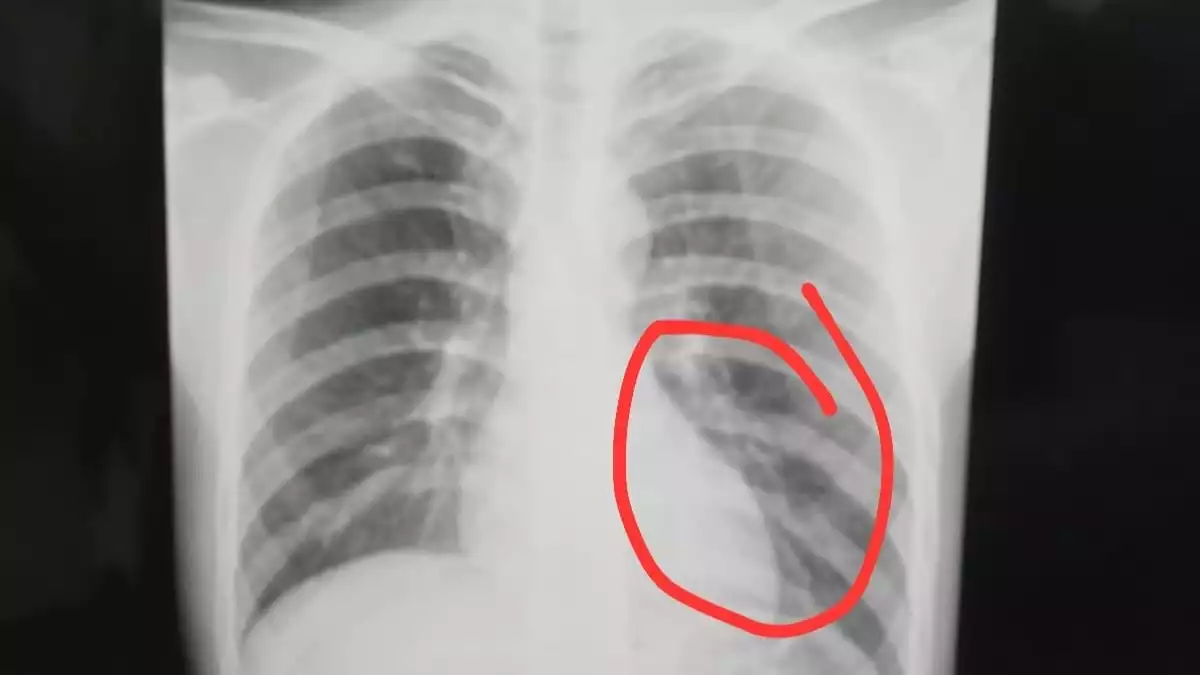

Foto dada Firman Nugraha, Korban Tendangan Kungfu Pemain PS Putra Jaya di Liga 4

Hasil pemeriksaan rontgen menunjukkan adanya retakan pada tulang rusuk bagian bawah, yang menempatkan cedera Firman dalam kategori serius dan berpotensi berbahaya bila tidak ditangani secara optimal.

“Hasil pemeriksaan rontgen menunjukkan adanya retakan pada tulang rusuk bagian bawah. Kondisi ini masuk kategori cedera serius dan berisiko,” ungkap Rudi.